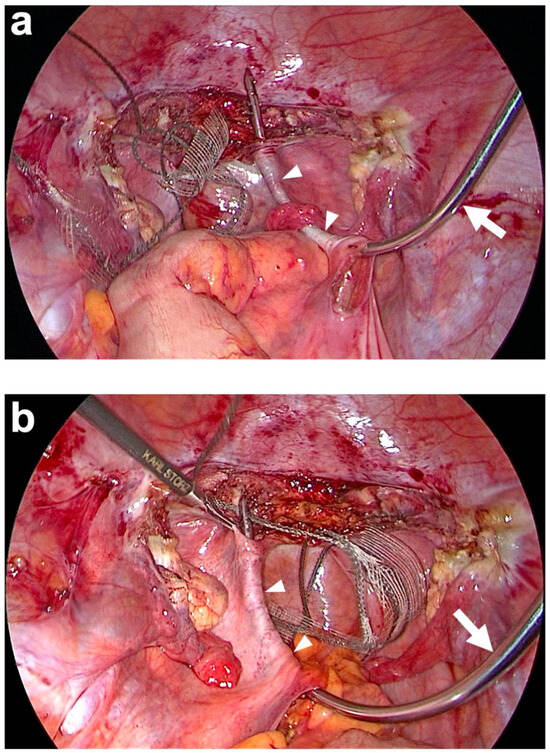

| Posterior fixation of left and right arm of PVDF structure (Figure 1) | At left and right prevertebral fascial layer at S1 with 2 interrupted, non-absorbable sutures each e within the defined locations at the PVDF structure. | At left and right prevertebral fascial layer on S1/promontory with 3 titanium helices each g within the defined locations at the PVDF structure (Figure 2 and Figure 7). |